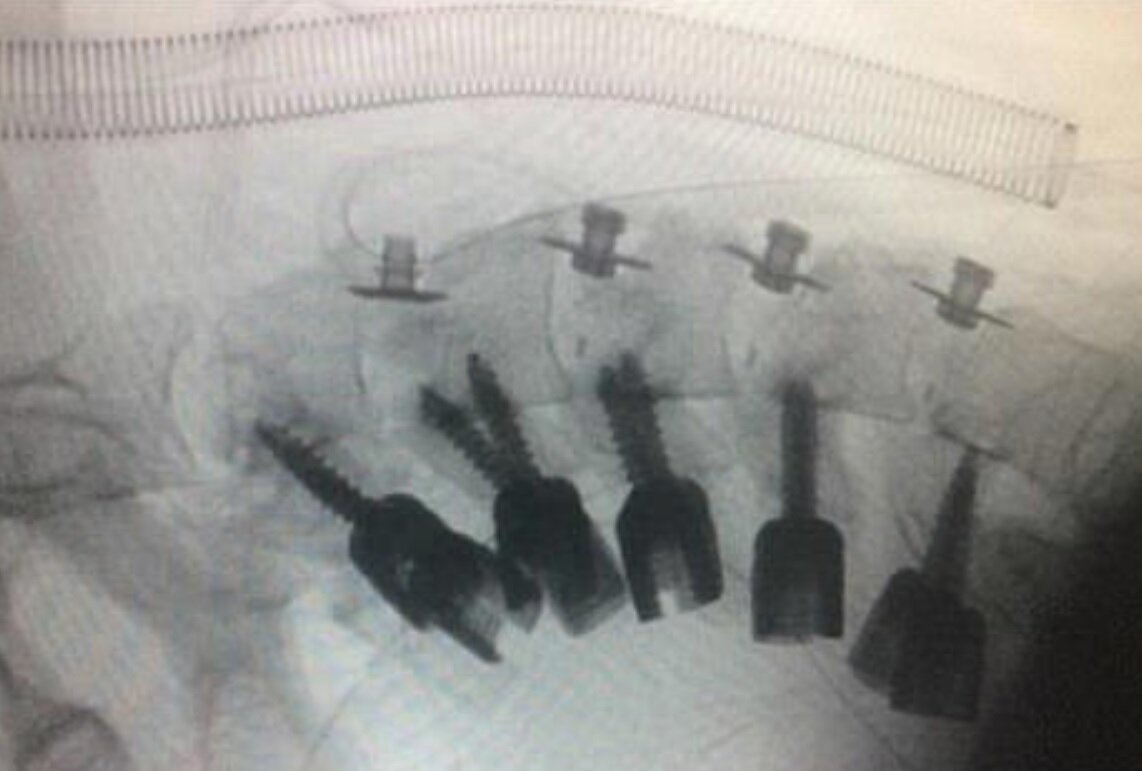

پزشکان گردن این جوان را جراحی کردند و با قرار دادن میلههای فلزی در استخوانهای گردن او، وضعیت گردنش را اصلاح کردند.